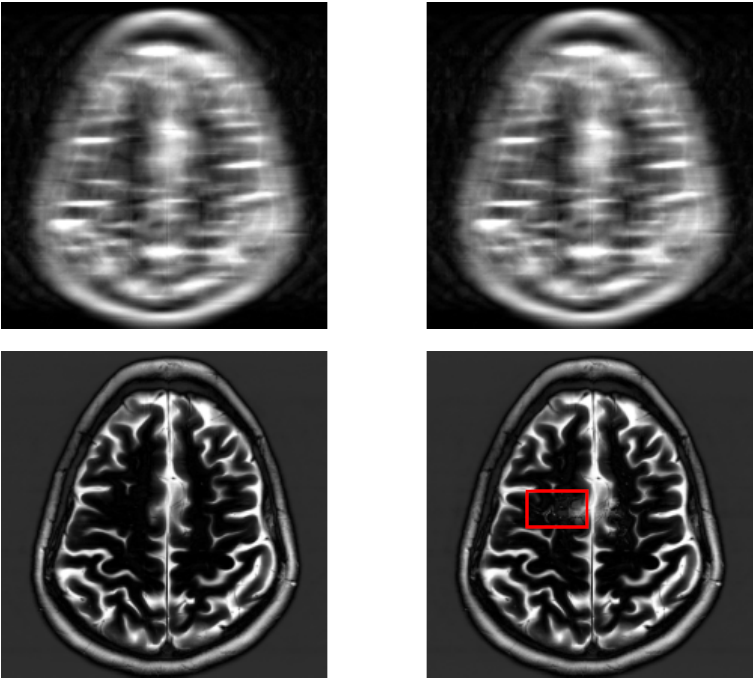

For a qualitative assessment of the results, we show some examples in figure˜0.B.1 for the UNet model and figure˜0.B.2 for the E2E-VarNet model of reconstructions where the attack was successful. These figures are structured as 2x2 panels of images where the first row displays the original and perturbed input samples and the second row displays the corresponding model-based reconstructions. Areas which we believe contain hallucinatory structures are highlighted in red.

We notice from LABEL:fig:unet-best1 and LABEL:fig:unet-best2 that the multi-coil images seem to be more vulnerable than the single-coil ones, in the sense that the resulting distortions are more severe for multi-coil data. The generated perturbations also seem easier to spot for single-coil data. This may be explained by the fact that perturbations in the multi-coil images can be more “spread out” across the coils, whereas with single-coil data this is not possible. This is consistent with the observation that vulnerability to adversarial examples increases with data dimensionality [14, 27]. Although we cannot compare to single-coil data for the E2E-VarNet, we do notice large distortions in LABEL:fig:varnet-best1 as well that go far beyond the boundaries of our inserted detail. On the multi-coil brain data, the hallucinations seem less severe for both models compared to the knee data, but the distortions can still be significant as they tend to resemble non-existent sulci. For knee images, the distortions appear to substantially change the structure of the knee joint, especially on multi-coil data.